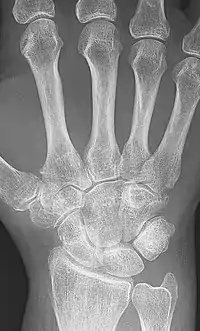

X-rays of the hands and feet are generally performed when many joints affected. In RA, there may be no changes in the early stages of the disease or the x-ray may show osteopenia near the joint, soft tissue swelling, and a smaller than normal joint space. As the disease advances, there may be bony erosions and subluxation. Other medical imaging techniques such as magnetic resonance imaging (MRI) and ultrasound are also used in RA.[20][68]